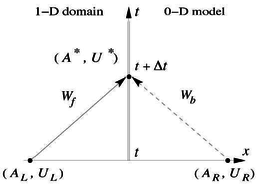

Boundary conditions from multiscale modeling of circulation: Another approach to impose the boundary conditions is to use reduced models, as 1D model or 0D (lumped) models. 1D and 0D models are mathematical models able to reproduce the systemic and pulmonary circulation. Figure 10 shows a standard approach to provide realistic local boundary conditions for 3D CFD simulations at the specific arterial domain using 1D models of the entire arterial tree and 0D models at the distal ends[83]. 1D model solves the Navier-Stokes equations under some assumptions (see appendix 9) and lumped models (0D models) can be derived from electrical circuit analogies where blood flow is represented by the current and arterial pressure by the voltage. Usually the electrical components of these circuits are resistances, inductances and capacitors. Where resistances represent arterial and peripheral resistance that occur as a result of viscous dissipation inside the vessels, capacitors represent volume compliance of the vessels that allows them to store large amounts of blood, and inductors represent inertia of the blood[75]. The values of these electrical components can be estimated from physical data of the subject [84][85]. This approach is quite used because it is capable to account for the effect of local pathological conditions on the whole circulatory system, providing realistic boundary conditions for the 3D problem [75][79][86].